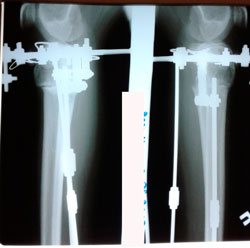

Дата операции - 08.06.2020

Дата снятия аппаратов 24.08.2020

Срок сращения - 75 дней.